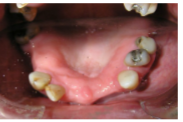

• Has a UL1 denture and hates it

• Does not like the margin on the UR1

• Does not want a fixed bridge UR1 to UL2

Extraction of the UR1

Single Implant placement UL1 for cantilever bridge